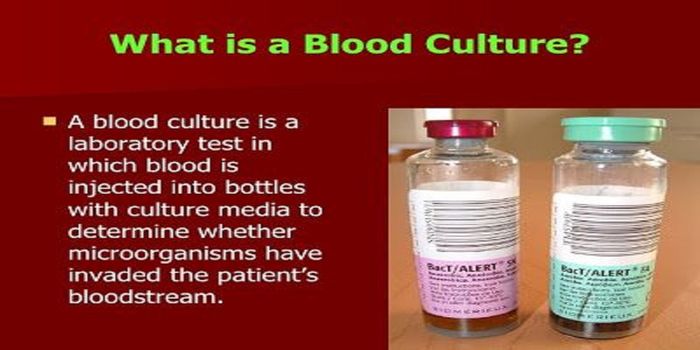

JUL 21, 2021MicrobiologyBlood culture is the most widely used diagnostic tool for the detection of bacteremia and fungemia. It is the most impor ...

FEB 20, 2019Health & MedicineConventional methods of identifying a positive blood culture require waiting for the blood culture broth to grow th ...